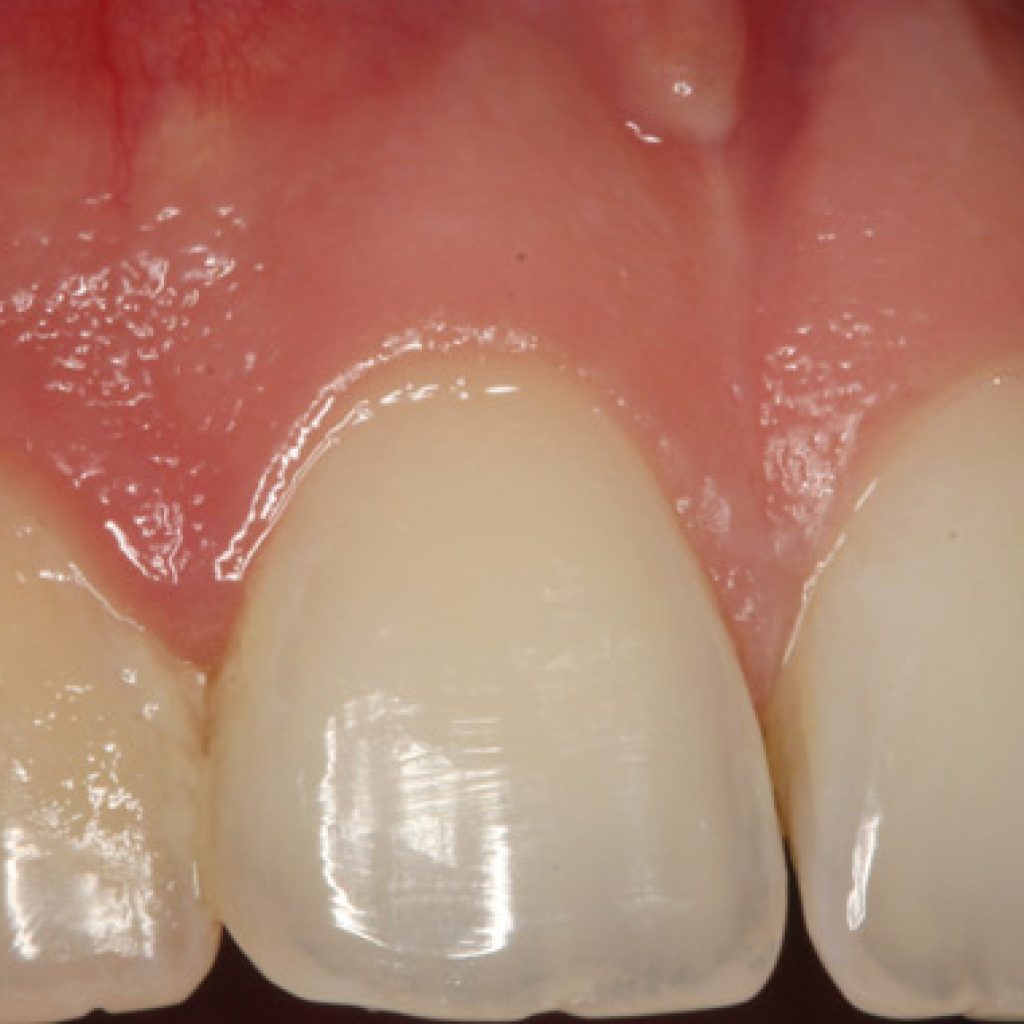

En la sociedad moderna la estética de la sonrisa está confirmanda como una preocupación muy importante en cuanto a las relaciones interpersonales, y representa un punto clave durante el proceso de toma de decisiones en pacientes que requieren rehabilitación oral compleja y combinada. Los datos de la literatura muestran que las personas atractivas son juzgadas […]